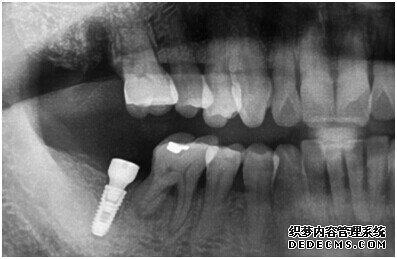

成功植入种植体后的效果图

种植体成功植入后的CT效果图